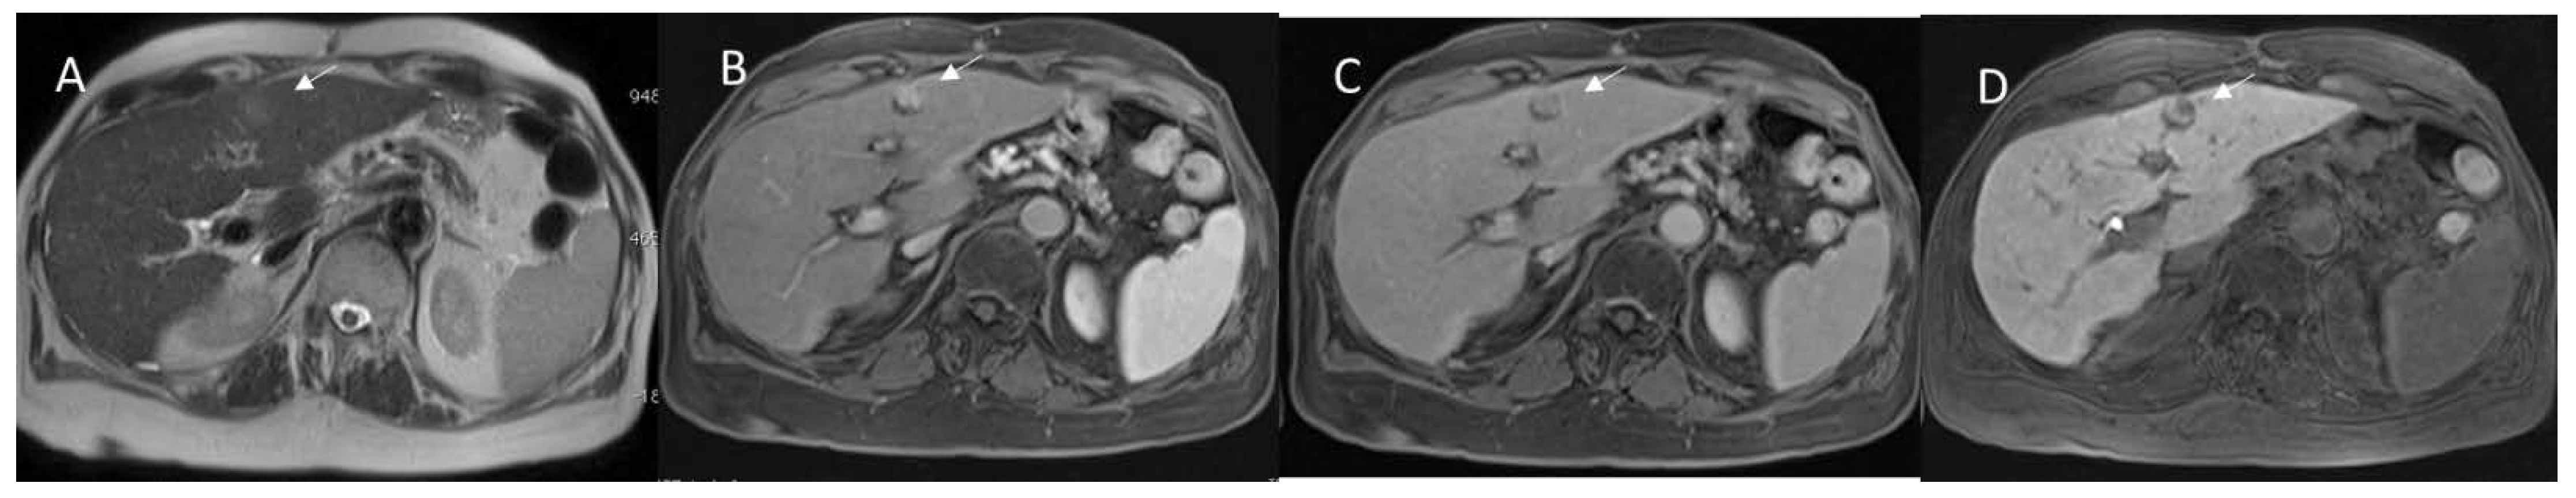

Figure 3. Colorectal mucinous liver metastases, assessed with non-liver-specific contrast agent. The lesion (arrow) shows hypointense signal in T1-W: (A) sequence; (B) very high hyperintense signal in T2-W; (C) restricted diffusion; and targetoid appearance during (D) arterial, (E) portal, and (F) late phase of contrast study.

With regard to contrast agents in MRI liver studies, today, two types of agents could be used. According to the different phase of patient management, the study protocols can include the possibility to administrate a liver-specific contrast (in pre-surgical settings) and a non-liver-specific contrast (in the characterization and staging phases). Liver-specific contrast agents can also be used to assess functional liver failure in both patients with hepatocellular carcinomas (HCC) (Figure 2) and in liver metastatic patients (Figure 3). Therefore, to understand the pattern of the lesion during the study of the contrast medium and the functionality of the liver parenchyma, the radiologist should clarify the type of agent used. Furthermore, the contrast agent is a drug and could cause a reaction, so these data should be reported in a SR.